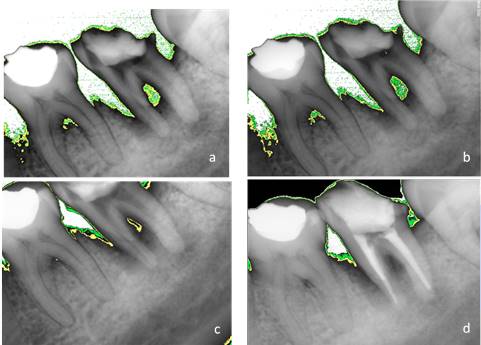

The intracanal medicament was replaced after 7, 15, and 21 days. An X-ray was taken at each appointment. Additionally, an analysis was conducted with Kodak software. The areas of periradicular bone density were digitally assessed at each appointment: white showed absence, green 2.5%, and yellow 7%.

Finally, after 28 days, the patient being asymptomatic and with no intracanal exudation, the practitioner decided to seal the canal system with gutta-percha with thermoplastic AH-Plus sealant. A final radiography is taken and compared to previous images (Fig. 3). The intermediate restoration was made with IRM. The patient was referred to the Dental Prosthesis Department of the School of Dentistry for crown rehabilitation.

During the treatment, the radiographic evaluations showed progressive bone apposition and, therefore, a process of repair of the periapical lesion. This is consistent with Toker’s findings28 in a study with rats with apical periodontitis: an increase in bone density was observed after the use of propolis. Pilegi’s in vitro study29 also provides evidence that propolis inhibits osteoclast maturation by promoting lesion repair.